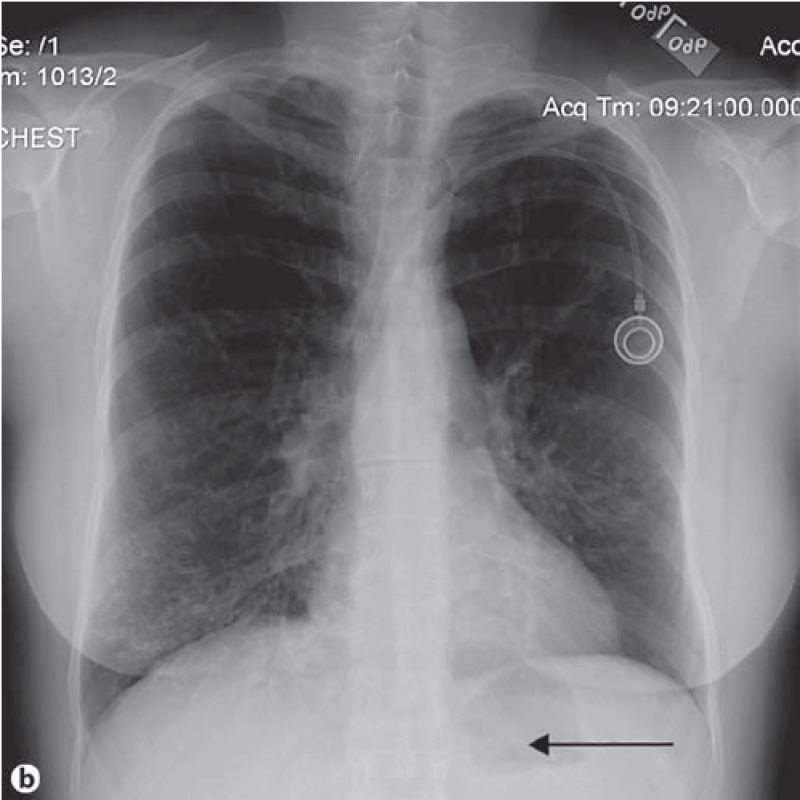

Exame de Imagem de Tomografia do Tórax

Exame de Imagem de Tomografia do Tórax

Exame de Imagem de Tomografia do Tórax

Medicom ExamesUm exame de imagem é uma fase do processo de diagnósticos e tratamentos. Um exame de imagem é uma forma de permitir que os médicos possam ver e... Cotar Agora Saiba Mais